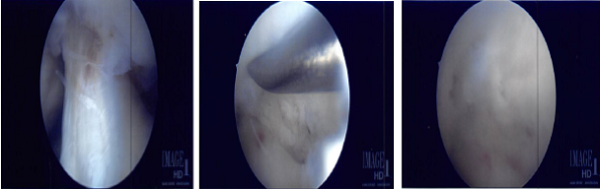

The scope was moved to the lateral compartment, where there was faying of the posterior horn near the root of the lateral meniscus. It was debrided using shavers and punch. The scope was moved to the patellofemoral joint, which was found to be in good condition.

The lateral meniscal tear was further debrided and the final pictures were taken. At the end of the procedure, micro punch was also used to put 4 to 5 holes into the intercondylar area.

Fat globules and fresh blood could be seen coming out of hose holes. The knee was irrigated copiously and closed using nylon #4-0. Dressing was done with Adaptec, 4×4, Web il, and Ace wrap.